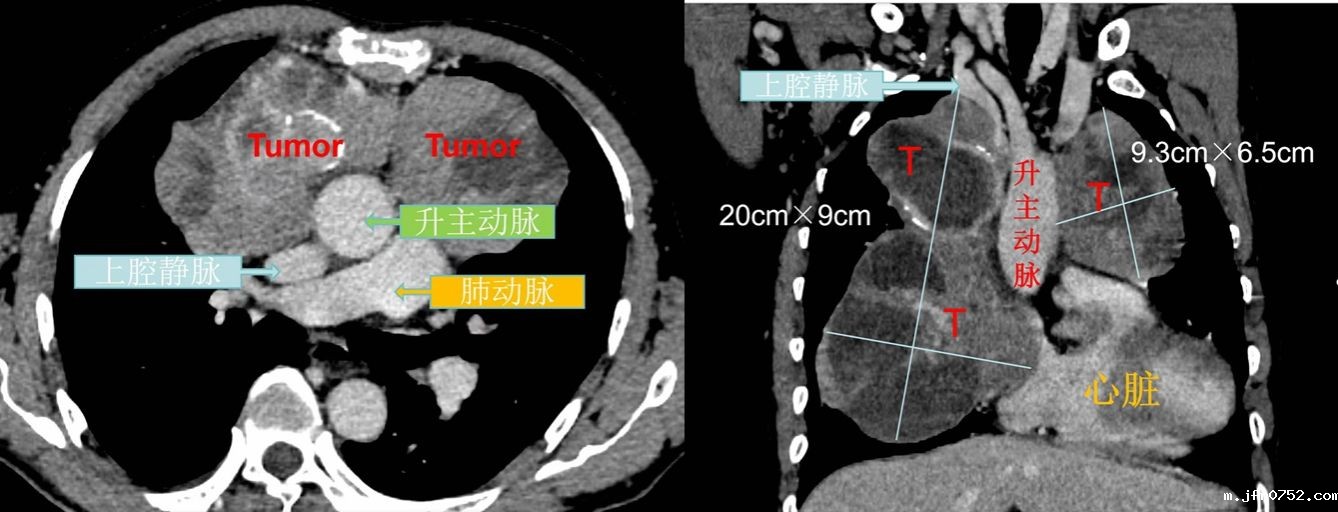

4月下旬,我院胸部肿瘤外科为1例巨大纵隔肿瘤患者成功实施纵隔肿瘤根治性切除手术。目前患者恢复良好,已顺利出院。2023年底,来自陕南的48岁魏先生因胸前压痛,就诊当...